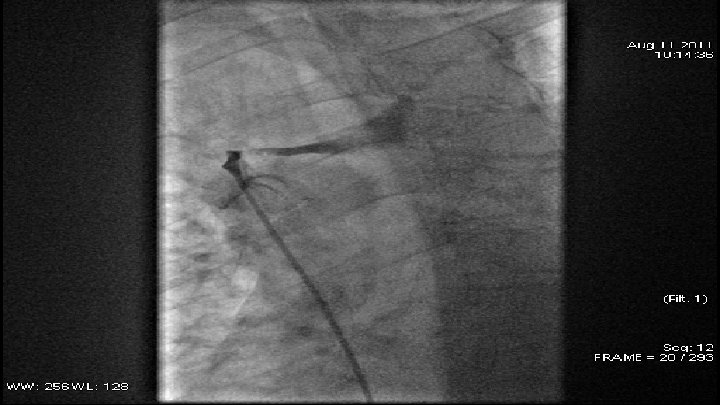

Case 1 q q q 66 y old patient May 2010 – small cell lung cancer was diagnosed April 2011 – venography - high grade stenosis of v. brachiocephalica billateral, PTA and stent implantation of v. brachiocephalica sinstra and baloon angioplasty of v. brachiocephalica dextra July 2011 – CT scan data for restenosis of v. brachiocephalica dextra August 2011 – venography - 90% restenosis of v. brachiocephalica dextra – after predilalatation was implanted stent.